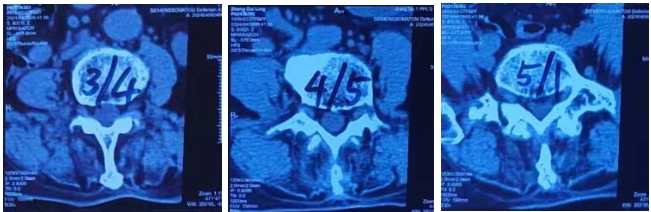

腰椎间盘CT: